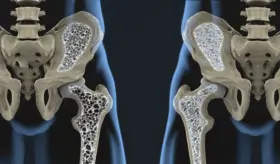

#InfografíaMSP La artrosis desgasta el cartílago que recubre las articulaciones, afectando su movilidad y provocando dolor, rigidez e inflamación. A medida que avanza, puede alterar por completo la estructura de zonas como rodillas, caderas, columna y manos.